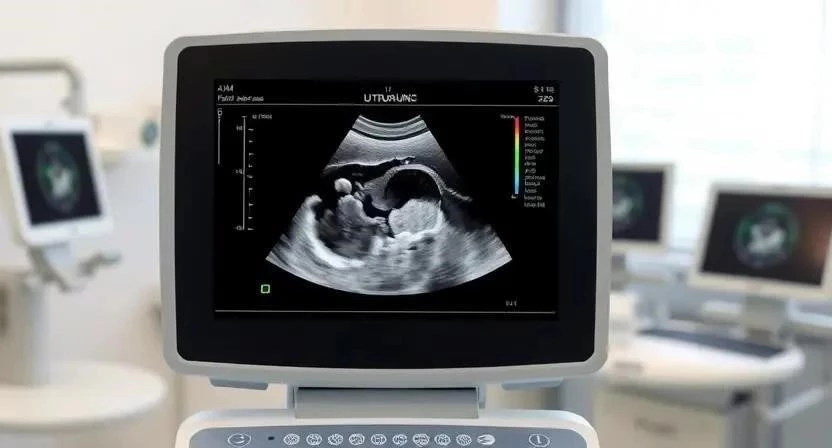

Для диагностики гинекологических заболеваний используются различные методы, такие как УЗИ органов малого таза, анализы крови и мочи, мазок на флору, кольпоскопия (осмотр шейки матки под увеличением), гистероскопия (осмотр полости матки с помощью эндоскопа). Современные методы диагностики позволяют выявить заболевания на ранних стадиях и назначить эффективное лечение. Важно выбирать клинику с современным оборудованием и опытными специалистами. Мне всегда нравилось, что в моей клинике врачи подробно объясняют результаты анализов и предлагают различные варианты лечения.